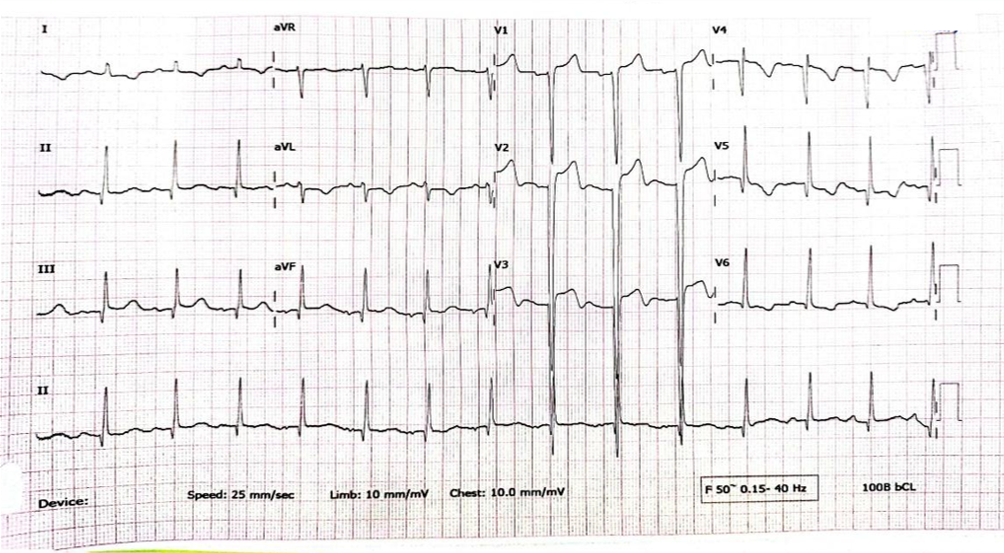

Relevant Test Results Prior to Catheterization

EKG showed normal sinus rhythm with ST segment elevation at V1-3 , inverted T wave at V4-6 , I ,aVL. Echocardiogram showed impaired LV systolic function, global wall hypokinesia, normal prosthetic aortic valve function with mild paravalvular leakage and bulging of aortomitral intervalvular fibrosa, suspected Aortomitral intervalvular fibrosa aneurysm. CT cardiac revealed pseudoaneurysm of the aortomitral intervalvular fibrosa with laminated thrombus with no LAA thrombus visualized.